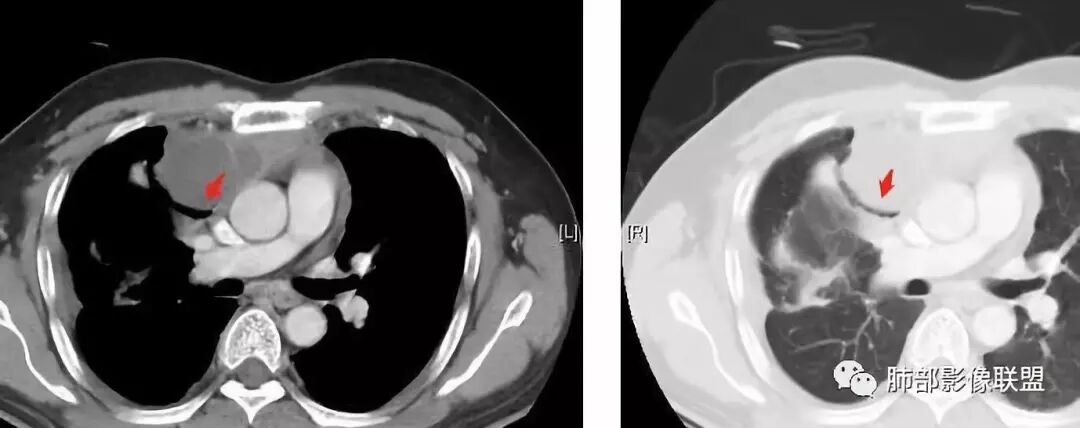

大家仔细看看积液中的游离气体;

不是支气管,是积气;是穿刺进去的;

囊内密度不一致

我认为囊张力高,积液中的气体均在周围,外侧、下方,囊内有间隔:各腔密度不一致;提示:囊腔属于前纵隔,不是包裹性积液;现在的问题:囊腔与内侧的病灶是否是一体的